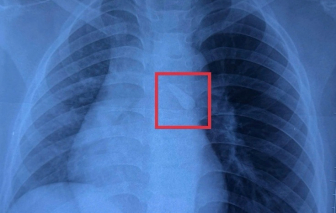

|

| Hai mẹ con chị Ánh Việt khi gặp nhau |